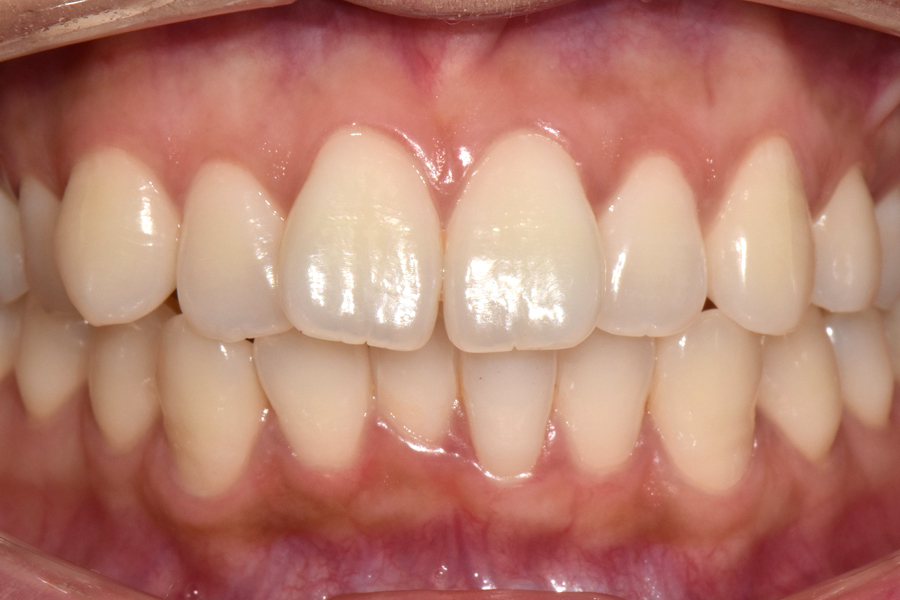

안녕하세요. 오늘은 다른 부분교정과는 다르게 클리피씨 장치를 이용한 부분교정 케이스에 대해서 알아보도록 하겠습니다. 보통 이렇게 앞니가 많이 삐뚤거리는 경우에는 부분교정으로 치료를 간단하게 할 수 있습니다.

보통 부분교정을 하는 경우 간단한 장치를 이용해서 교정을 하시는데 위 환자분과 같은 케이스는 치아 모양과 어금니가 물리는 것도 양호하신 편이여서 조금 더 정밀한 교합을 위해 클리피씨 교정을 진행하였습니다.

교정을 3월에 시작하셨는데 5개월이 지난 후의 모습입니다.

부분교정의 경우에는 중심선을 맞추기가 굉장히 어려운데 환자분 교합이 괜찮으시고 치아도 잘 움직여주셔서 가운데 선을 맞출 수 있게 되었고, 교합도 거의 전체교정을 한 것처럼 아주 예쁜 효과를 얻을 수 있었습니다.

때문에 환자분께서도 교정 결과에 굉장히 만족을 하셨고, 웃었을 때도 자연스럽게 치아 모양이 예쁘게 유지되는 것을 보실 수 있습니다.